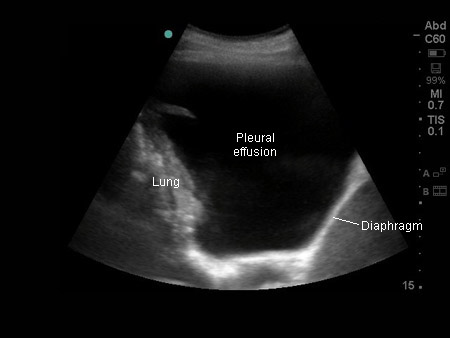

[Figure caption and citation for the preceding image starts]: Thoracic ultrasound image of large, simple pleural effusionFrom the collection of Dr Nicholas Maskell; used with permission [Citation ends].